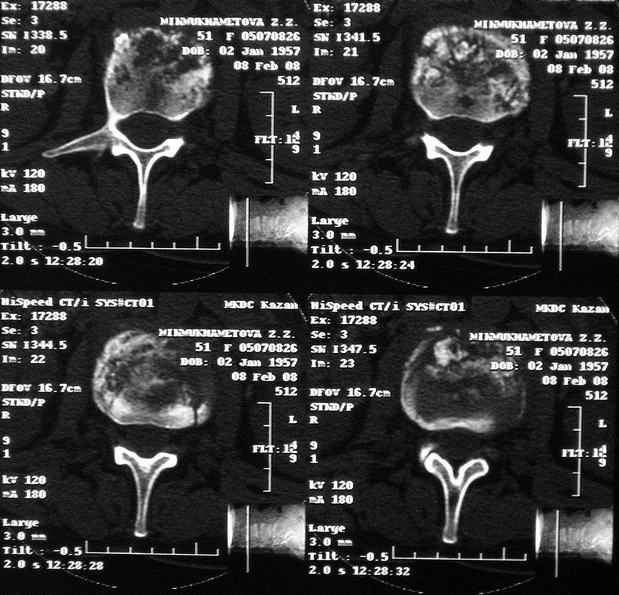

Отправляю MRI в динамике, снятые с пленки на фотоаппарат.

|

MRI через три недели

По данным представленных КТ и МРТ у больной имеется достаточно выраженная степень деструкции тел позвонков (около 30% общей костной массы тела позвонка), что определяет высокий риск возникновения патогических переломов и появления локальной кифотической деформации на этом уровне.

Судя по снимкам похоже идет речь о спинальном остеомиелите для диф диагноза стоит провести черезкожную пункционную биопсию(с помощью КТ)